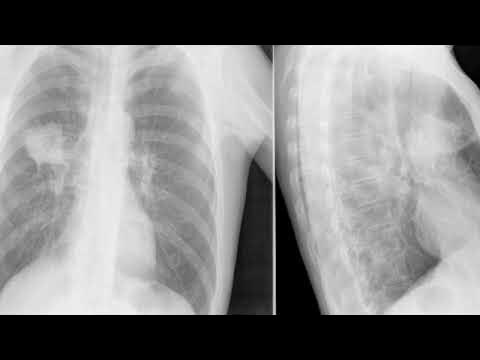

Рак лёгких: первые признаки, которые легко пропустить

• рентген и компьютерная томография,